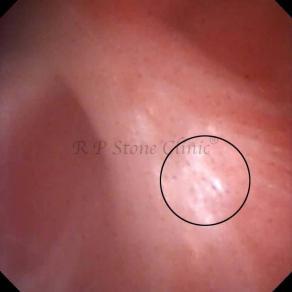

These images are taken as snap shots from the video recording of RIRS Surgery done at our hospital. These are Randall’s Plaques seen with Digital FLEX XC & Digital FLEX XC S. The cream or whitish patches are seen on the tips of RENAL PAPILLAE as seen in images below.

The Below Images Show Small Stones attached to the Renal Papillae.